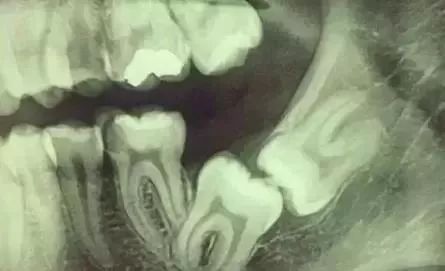

先放几张图,让你们涨涨姿势,不拍片根本不知道你的牙齿长得会有多奇葩!

下图圈出来的地方或多或少都有点龋齿,但是有些你并不能看见。这些龋齿还浅不会让你有什么感觉,顶多吃东西塞牙,和冷水敏感而已。

每颗牙都有所龋坏

暗的部位说明龋齿已经非常严重了!

龋坏接近牙髓了